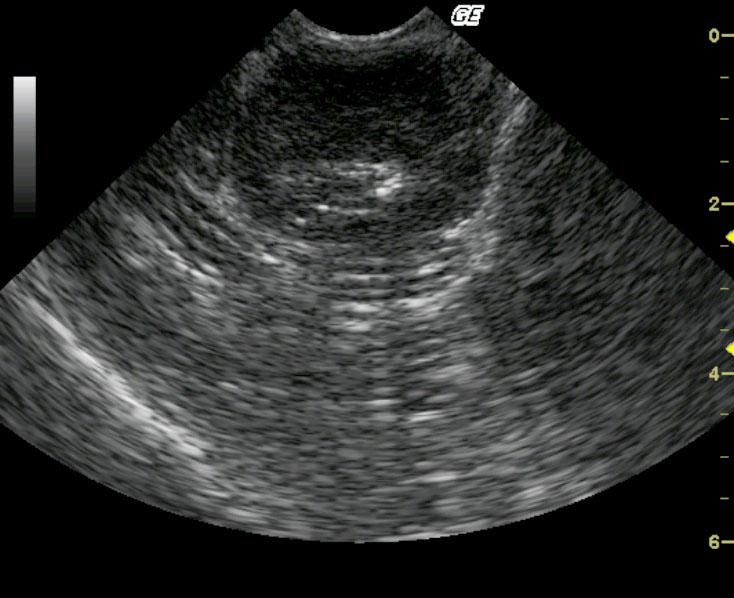

This MN 10-year-old DSH was presented for partial anorexia and weight loss and the physical examination revealed palpably thickened intestines. A CBC and blood chemistry profile revealed a mild leukocytosis with slightly elevated ALT and slightly elevated lipase.